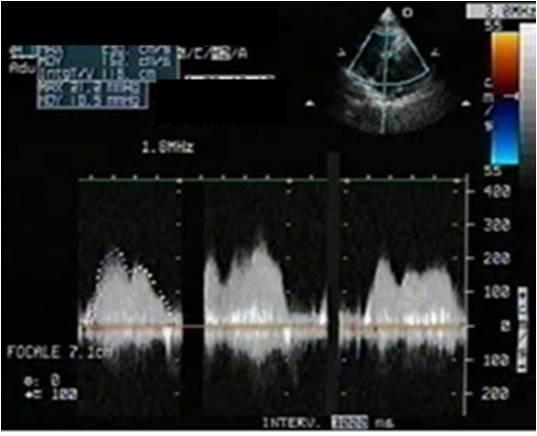

We report the case of a 64-year-old non-immunodeficient Caucasian man, with cardiac tamponade and paroxysmal third-degree atrioventricular block. Echocardiography revealed the presence of a large pericardial effusion with signs of tamponade and a right ventricular mass was suspected. Scanner investigations clarified the sites, extension and anatomic details of myocardial and pericardial infiltration. Surgical resection was performed due to the rapid impairment of his cardiac function. Analysis of the pericardial fluid and histology confirmed the diagnosis of non-Hodgkin large B-cell lymphoma. He was treated with chemotherapy.

我们报告一例64岁非免疫缺陷的白种男性病例,该患者患有心脏压塞和阵发性三度房室传导阻滞。超声心动图显示存在大量心包积液并有压塞征象,怀疑有右心室肿块。扫描检查明确了心肌和心包浸润的部位、范围及解剖细节。由于其心功能迅速恶化,遂进行了手术切除。心包液分析和组织学检查确诊为非霍奇金大B细胞淋巴瘤。他接受了化疗。